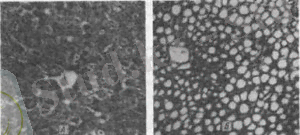

Микроскопиялық өзгерістер. Кетозға тән және тұрақты өзгерістер бауырда болады. Диффузды майлану инфильтрациясы көмірсулық және түйірлі дистрофиямен бірге қосақтапсып жүреді. Мұнда митохондриялар ісінеді, гранулалық қабат цистерналары кеңейеді, тегіс цитоплазмалық тор цистерналар саны көбейеді, олар көпіршіктенеді. Созылмалы кетозда бауырда қан тамырлық өзгерістерден басқа гепатоциттердің дистрофиялық майлануы, түйірлі дистрофиясы, некробиозы байқалады.

Паренхиматозды органдарда, әсіресе бауырда, бүйректе (түсті кесте. XII - А) және жүректе айқын дистрофиялық және гемодинамикалық өзгерістер анықталады. Бауыр көлемі жағынан айтарлықтай жоғарылайды (кейде 1, 5-2 есе), ақшыл консистенциясы, сарғыш-сарғыш түсті. Мүшенің кесілген беті майлы болып келеді. Бүйректің мөлшері, ереже бойынша, үлкейген, қабаттар арасындағы шекаралар айқын көрсетілмеген, кеңейтілген қабық сарғыш реңкпен. Медуллада тамырлар қанға толып кетеді. Эпикардий астында, жүрек түбінде, коронарлық тамырлардың бойында айтарлықтай май шөгінділері бар. Миокард әр түрлі дәрежеде қарыншалардың ақырын, анемиялық, миогендік кеңеюі болып табылады.

Патогистологиялық өзгерістер. Жедел біріншілік кетоз кезінде бауырдың диффузды майлы инфильтрациясы әдетте көмірсулармен және түйіршікті деградациямен біріктіріледі. Гидролаза белсенділігінің ығысуы және Кребс-Эмбден-Мейерхоф циклі ферменттерінің белсенділігінің төмендеуі байқалады. Электронды микроскопиялық зерттеу кезінде бауырдағы майдың үлкен тамшылары жасушаның көп бөлігін алып жатқандығы, ал цитоплазманың қалған бөлігі ядролармен бірге жасушаның перифериясына ығыстырылғандығы, атрофиялар анықталды. Гепатоциттердің органеллаларында SDH және ATP-асе белсенділігі күрт төмендейді (Жаров, 1975) ; сиыр бауырындағы стромальды өзгерістер Купфердің жасушаларының фагоцитарлық белсенділігінің жоғарлауымен, сондай-ақ синусоидтарда және жеке өлі бауыр жасушаларының орнында макрофагтар мен лимфоидты жасушалардың ұсақ кластерлерінің түзілуімен сипатталады.